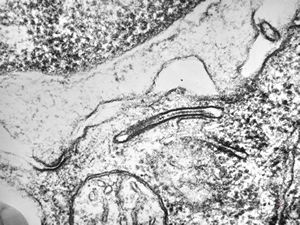

M,11y. | mast cell - skin

M,3y. | mast cell - n. suralis, Krabbe globoid leukodystrophy

F,23y. | mast cell - n. suralis, demyelinating neuropathy